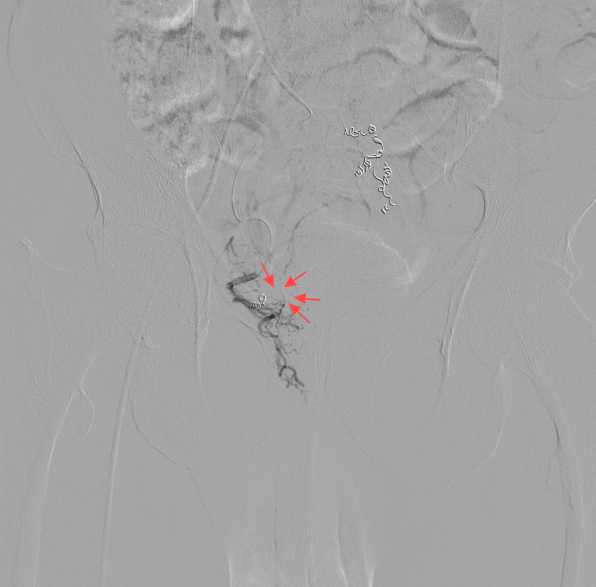

术中髂内动脉造影可见直肠中动脉部分与痔血管相通